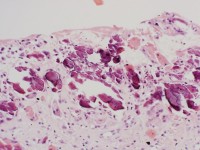

Diagnostiek:De diagnose wordt gesteld op het

histologisch beeld. In de oppervlakkige dermis zijn kalkdeposities aanwezig.

De kalkdeposities zitten niet in de vaten. Er zijn vreemdlichaamreuscellen

en lymfocyten in de dermis aanwezig. De dermis toont fibrose. Calcium

spiegels normaal.